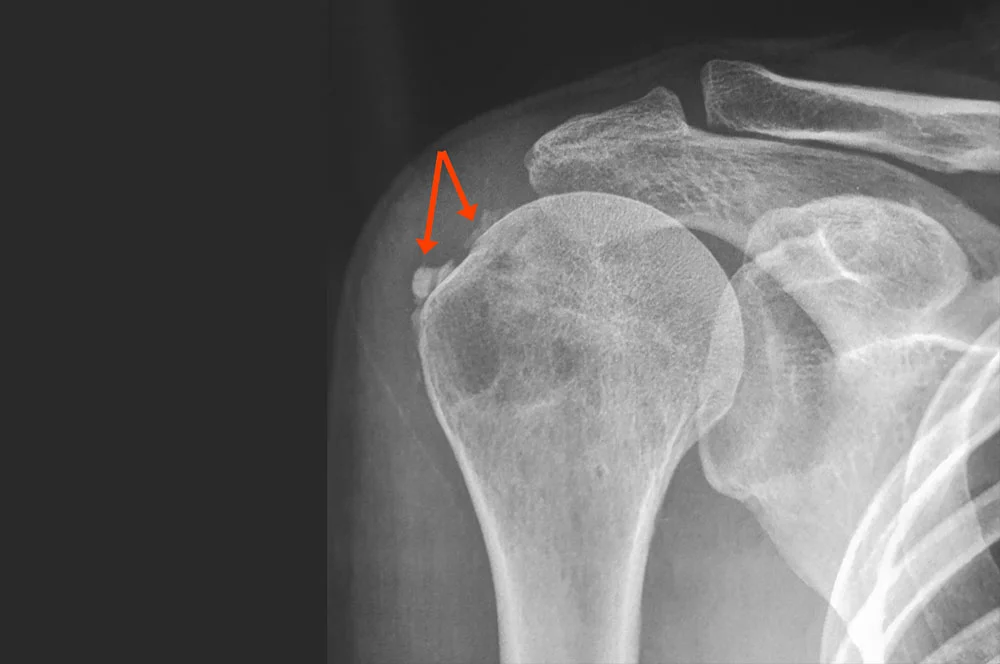

Η διάγνωση επιτυγχάνεται μέσω κλινικής εξέτασης και απεικονιστικού ελέγχου όπως:

• Απλή ακτινογραφία ώμου, όπου διακρίνεται η ασβεστοποιημένη εναπόθεση

• Υπερηχογράφημα ή μαγνητική τομογραφία για εκτίμηση της φλεγμονής και του μεγέθους της ασβεστοποίησης